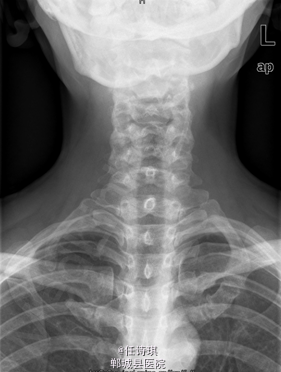

女,46岁8月,因“颈部不适3年,右上肢软弱疼痛伴双下肢胀痛1年”入院。3年前无明显诱因出现颈部不适,以局部胀痛为主,劳累后加重休息后可缓解,不伴上肢放射痛。遂未予特殊处理。1年前出现右上肢酸麻肿痛,以肘关节疼痛和手部皮肤麻木为主,行走约10分钟后自觉双小腿后侧胀痛,休息后可缓解。在当地医院诊断为“网球肘、颈椎病”予以对症治疗,但上述症状无明显改善。行MRI、CT等检查,诊断为“C2椎管内肿瘤”,未予特殊治疗。为求进一步诊断今日由门诊以“C2椎管内占位,性质?”收入院

专科查体:视:脊柱无明显畸形。触:颈胸部各棘突无明显压、叩痛。四肢肌张力正常,右手皮肤触觉减退。动量:右侧上肢肌力IV级,左侧肢体V级。右侧上肢腱反射活跃,双侧膝腱反射活跃,跟腱反射正常引出。Hoffman征阳性,Babinski征未引出。外院MRI示:C2椎管内脊髓背侧占位病变,脊膜瘤可能。T2椎体内异常信号,多为血管瘤。。

初步诊断:1、颈2节段椎管内占位伴不全四肢瘫(Frankel D):脊膜瘤?黄韧带骨化? 2、胸2椎血管瘤 处理:全麻下行经后路颈2全椎板切除、椎管探查减压、椎管内占位切除活检术,